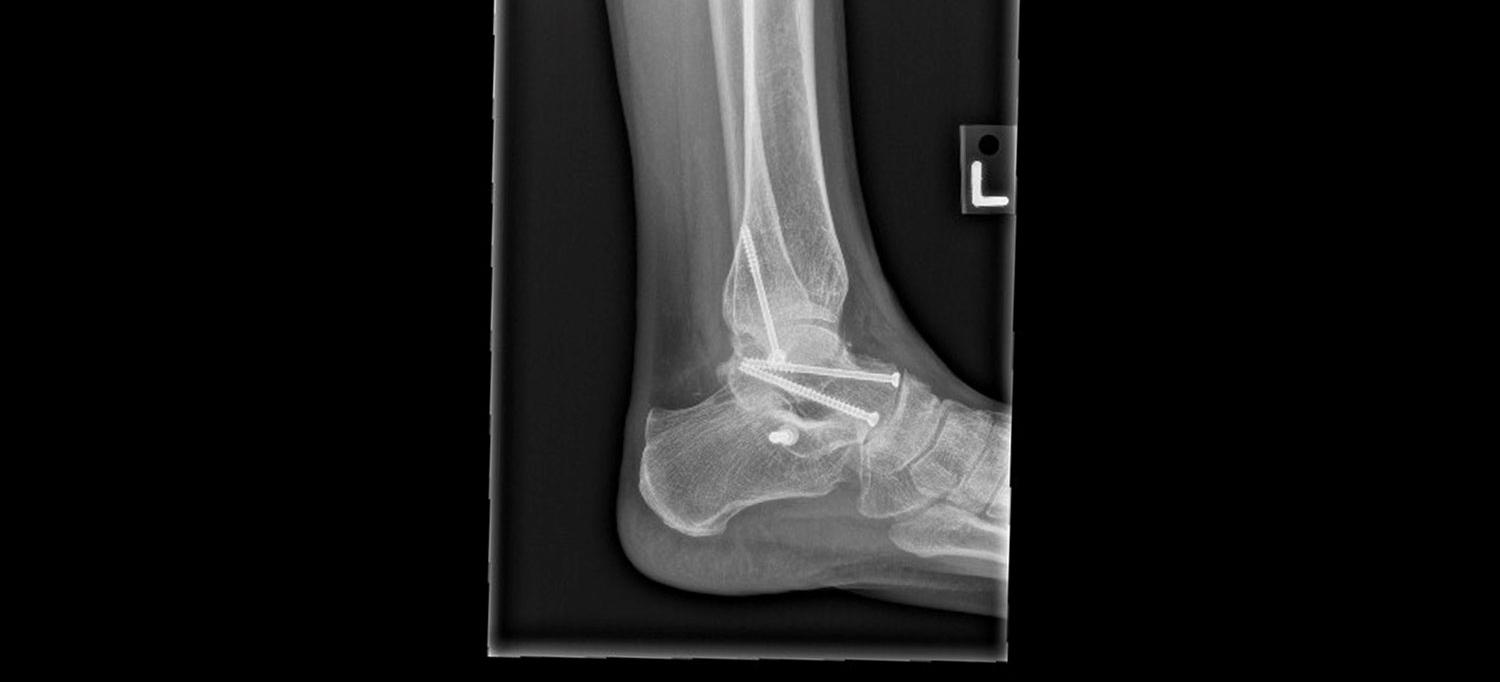

Four screws were used to repair the complex breaks in Martynka Wawrzynia’s ankle, leg, and heel.

Wawrzyniak ended up breaking her talus, fibula, and calcaneus—bones in the ankle, leg, and heel—in her fall. After failing to find a local emergency department that was open on a Sunday afternoon upstate, she headed home to New York City. The following morning Wawrzyniak went to a local urgent care practice that sent her straight to NYU Langone’s emergency department, where she was referred to Nirmal C. Tejwani, MD, a professor in the Department of Orthopedic Surgery at NYU Grossman School of Medicine and site chief of NYU Langone Orthopedic Hospital.

In surgery, Dr. Tejwani placed four screws in Wawrzyniak’s ankle and heel to repair the complex breaks. Her leg was not able to bear any weight for eight weeks, and she was on crutches for four months. To learn how to walk again, she began physical therapy recovery as soon as possible at a Jag One physical therapy practice near her home in Greenpoint, Brooklyn. But even a year later, Martynka was still limping and had difficulty with the range of motion in her ankle, which was limiting her in her active lifestyle of climbing, surfing, and running.